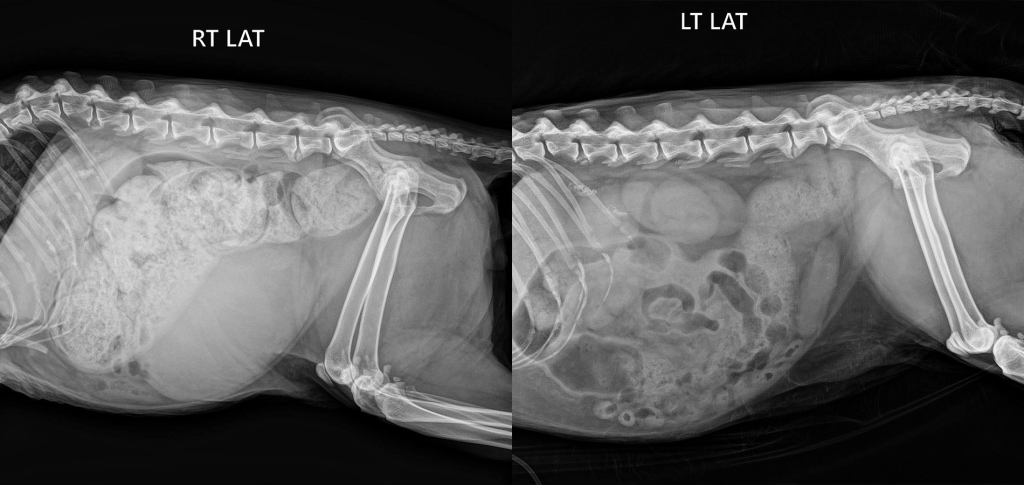

(кошка 7 лет: в течение 7 дней трудности с дефекацией, отсутствие стула в течение последних 4-х дней)

Основной метод диагностики копростаза – это рентген брюшной полости. Рентгенография позволяет определить наличие переломов, аномалий в строении, наличие инородных тел в просвете кишки, визуализировать рентгеноконтрастные новообразования в брюшной полости и кишечнике.